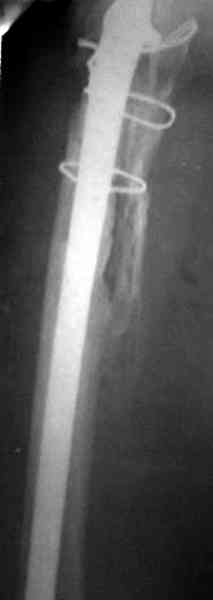

Для спейсера в бедро использовал старый длинный бедренний компонент меньшего диаметра, облепленный со всех сторон цементом с антибиотиком.

Наглухо ушитая рана с дренажом зажила первично, после чего с больной потерял контакт, и только недавно, через 8 лет я осмотрел её. Она без проблем нагружает на конечность и передвигается с помощью трости. От окончательной операции по реконструкции отказывается, довольная результатом.

Имеются литературные данные, когда спейсер держали не более 6 месяцев, но этот случай бьет все рекорды, может быть для наших людей, обременных финансовыми трудностями, нужна другая шкала оценки сроков нахождения спейсеров.

и последние снимки.